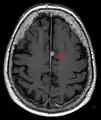

Brain regions on T1 MRI

T1 (note CSF is dark) with contrast (arrow pointing to meningioma of the falx)